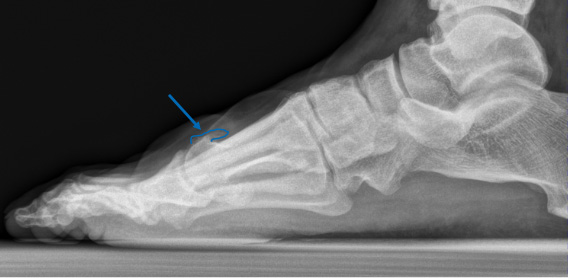

Ein Röntgenbild kann die Diagnose schliesslich sichern. Darauf ist sichtbar, dass der Gelenkspalt verschmälert ist, da sich der Knorpel abgenutzt hat. Zudem lassen sich die typischen Osteophyten und Überlastungen am gelenkangrenzenden Knochen in Form von Skleroselinien (Knochenverhärtung) und Zysten identifizieren.